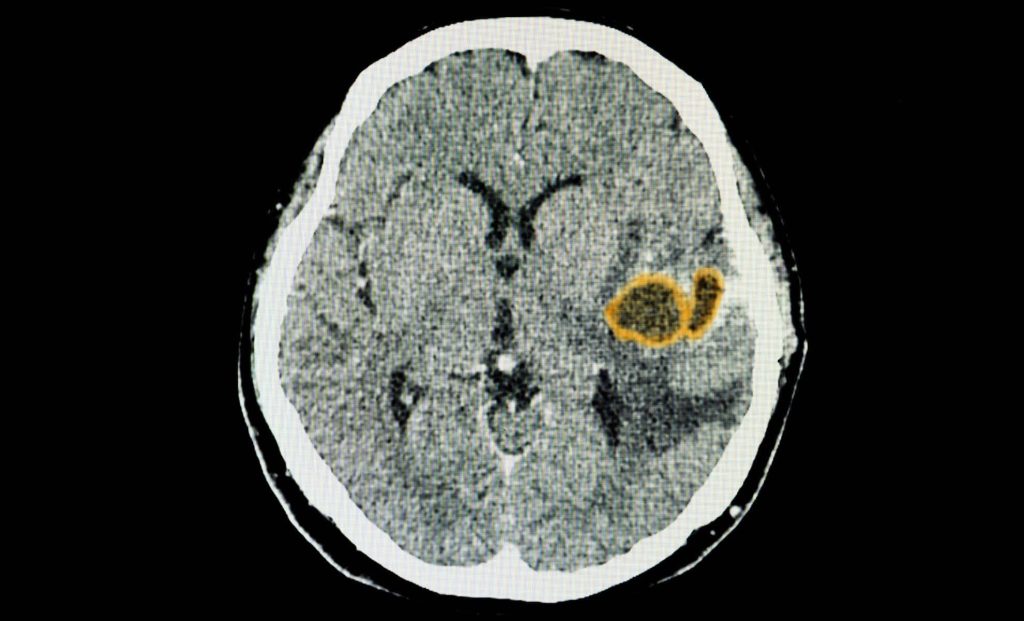

Think ahead! It’s important to treat your brain like a retirement fund — the earlier you invest, the better it

A common parasite known for silently embedding itself in the brain has revealed a new survival strategy: hijacking the very